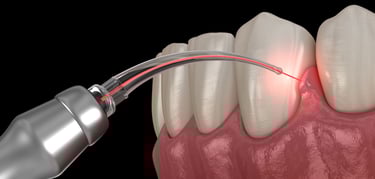

Laser Treatments

Laser dentistry potentially offers a more comfortable treatment option for a number of dental procedures involving hard or soft tissue compared to drills and other non-laser tools.

LASER stands for “light amplification by the stimulated emission of radiation.” The instrument creates light energy in a very narrow and focused beam. This laser light produces a reaction when it hits tissue, allowing it to remove or shape the tissue.

How are laser treatments performed?

The two main types of procedures used for laser dentistry are hard tissue and soft tissue procedures. Hard tissue refers to the teeth, and soft tissue refers to the gums.

Common soft tissue procedures include: